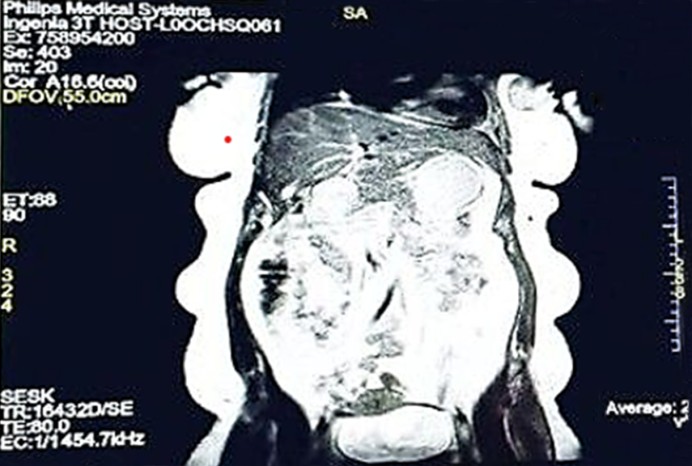

A 38-year-old woman, with no known comorbidities or previous TB exposure, presented with swelling in the left axilla for 6 months and a palpable lump in the left breast for 3 months. The breast lump was associated with intermittent pain over the past month, with no history of nipple discharge, weight loss, fever, or trauma. Vitals were stable, and systemic examination was unremarkable. On local examination, both breasts were symmetrical without any skin changes, such as ulceration, dimpling, or peau d'orange appearance. The nipples appeared normal. A 4 × 3 cm firm, mobile lump was palpated in the upper outer quadrant (4-5 o'clock position) of the left breast. Additionally, a 3 × 2 cm palpable lymph node was noted in the left axilla. The right breast and axilla were unremarkable. The differential diagnosis included both malignancy and TB. The Mantoux test was positive, showing 15-mm induration. A core-needle biopsy of the breast lesion was performed and submitted for histopathological evalu- ation and microbiological testing, including Ziehl-Neelsen (ZN) staining and the GeneXpert MTB/resistance to rifampicin (RIF) assay. The results of these investigations are presented in Fig. 1. MRI revealed two well-defined lesions in the lower and outer quadrants of the left breast, measuring 2.6 × 2.0 and 3.0 × 2.0 cm, respectively. Both lesions appeared hypointense on T1-weighted images and hyperintense on T2-weighted images, with rim enhancement suggestive of necrotic or infective components. Additionally, a significantly enlarged left axillary lymph node measuring 7.3 × 3.8 cm was noted. These findings were categorized as per the Breast Imaging Reporting and Data System (BI-RADS) VI and are shown in Figs. 2 and 3. Histopathological examination revealed features consistent with infiltrating ductal carcinoma. Granulomatous inflammation with caseous necrosis was noted in adjacent areas (Fig. 4). ZN staining of the biopsy specimen identified acid-fast bacilli. The GeneXpert MTB/RIF assay detected MTB DNA with an indeterminate result for rifampin resistance. Despite this, rifampin was included in the initial treatment regimen based on clinical judgment and in accordance with national TB control guidelines while awaiting further sus- ceptibility results. The patient underwent a modified radical mastectomy. Postoperatively, anti-tuberculous therapy was initiated using the standard 6-month regimen, consisting of isoniazid, rifampin, pyrazinamide, and ethambutol for the initial 2 months, followed by isoniazid and rifampin for remaining 4 months. Vitamin B6 supplementation was also initiated. The oncologic treatment was tailored based on the tumor stage and histological grading. The patient is currently under regular follow-up, with no evidence of disease recur- rence or TB reactivation.

The coexistence of tuberculous mastitis and infiltrating ductal carcinoma of the breast represents a rare and diag- nostically challenging clinical case. This rarity is due in part to the relative resistance of the breast tissue to MTB infection. This phenomenon is attributed to factors such as limited lymphatic supply, sparse reticuloendothelial tissue, and high oxygen content, which are unfavorable for mycobacterial proliferation. Consequently, breast TB accounts for <0.1% of all breast lesions, even in TB-endemic regions3,4. The simul- taneous presence of TB and malignancy in the breast can lead to significant diagnostic confusion. Both conditions can exhibit similar clinical features, including palpable mass, axillary lymphadenopathy, and skin changes. Radiologically, both TB and carcinoma can appear as irregular, speculated masses on mammography or as hypoechoic lesions on ultrasonography. MRI findings are often inconclusive because both lesions may exhibit rim enhancement and hyperintensity on T2-weighted images. In the present case, the MRI findings indicated a BI-RADS VI lesion, necessitating further histopathological evaluation5. Histologically, TB is characterized by granuloma- tous inflamation with caseous necrosis and the presence of Langhans giant cells, whereas carcinoma is identified by malignant epithelial cells with nuclear atypia and stromal in- vasion. In the present case, both histopathological patterns were evident. This concurrent pathology was further con- firmed by ZN staining and the GeneXpert MTB/RIF assay, which detected MTB DNA. The GeneXpert result indicated an indeterminate status of rifampin resistance. Despite this, rifampin was incorporated in the anti-TB regimen based on World Health Organization guidelines and national TB proto- cols, which recommend initiating first-line treatment while waiting for the results of further susceptibility testing unless resistance is confirmed. This clinical decision was justified by the absence of risk factors for multidrug-resistant TB and the patient's good clinical response to the standard regimen6. The immunological interplay between chronic TB and carcino- genesis is still being investigated. Some studies have sug- gested that chronic inflammation and cytokine release in TB may contribute to DNA damage and malignant transform- ation. Conversely, malignancy-induced immune suppression may reactivate latent TB. However, the precise mechanisms remain speculative and are not yet fully understood7. Several studies have documented either sequential or simultaneous occurrence of breast carcinoma and TB8-10; however, most studies are limited to older age groups or isolated case series. The presented case differs in that it presents in a relatively younger woman (aged 38 years) with no significant comor- bidities or immunosuppression. Unlike most published reports, the present report highlights the use of molecular diagnostic tools (GeneXpert), which aided in the rapid identification of TB. Although Pandya J reported moderate sensitivity (83.3%) and high specificity (99%) for GeneXpert in tuberculous mastitis11, few case reports have discussed its utility in cases of coexisting carcinoma and TB12,13. This underscores the originality and clinical novelty of this report. The coexistence of both TB and carcinoma requires an individualized thera- peutic approach. In the presented case, the patient under- went surgical excision for carcinoma, followed by a standard anti-TB regimen. This approach ensured that neither disease was undertreated. Importantly, oncologic treatments such as chemotherapy may exacerbate or reactivate latent TB, reinforcing the need for thorough screening and concurrent TB management in endemic regions.